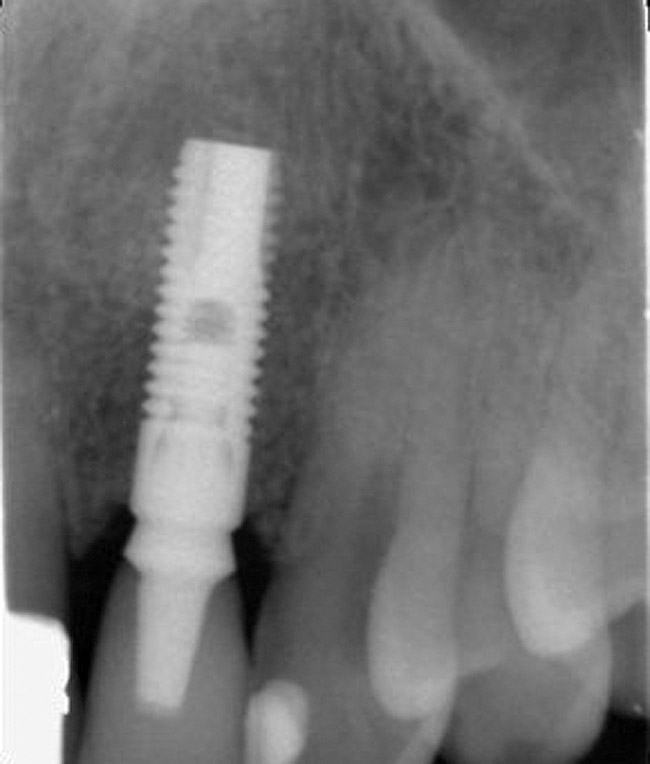

Figure 2  Identification of sufficient inter-radicular space: The radiographic representation of inter-radicular space (Fig 2) reveals abundant space for a single-tooth implant; at the alveolar crest, > 6 mm of interproximal space is available for placement of a 4-mm implant without encroaching on bone and periodontal ligament at the adjacent teeth. The 5-year-follow-up radiograph (Fig 3) reveals the interproximal maintenance of bone at this implant/abutment interface and adjacent teeth, in part due to proper planning and implant placement.

Figure 2

Figure 3  Identification of sufficient inter-radicular space: The radiographic representation of inter-radicular space (Fig 2) reveals abundant space for a single-tooth implant; at the alveolar crest, > 6 mm of interproximal space is available for placement of a 4-mm implant without encroaching on bone and periodontal ligament at the adjacent teeth. The 5-year-follow-up radiograph (Fig 3) reveals the interproximal maintenance of bone at this implant/abutment interface and adjacent teeth, in part due to proper planning and implant placement.

Figure 3